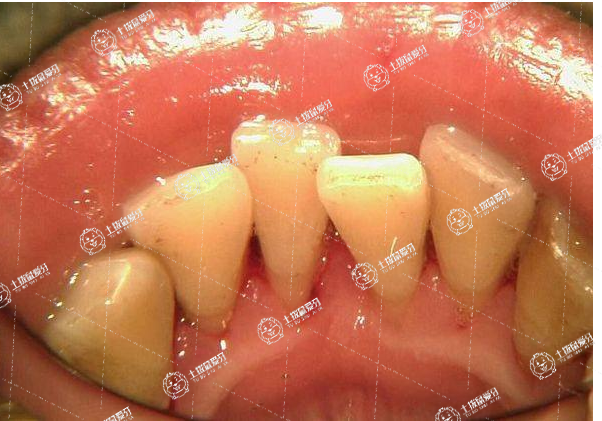

牙齒正畸,是通過在牙齒表面粘接托槽,通過施加矯治力進(jìn)行整體移動(dòng),從而改善錯(cuò)頜畸形。30歲進(jìn)行正畸不算晚,因?yàn)樵谌说囊簧醒啦酃嵌伎梢赃M(jìn)行改建,只要牙周是健康的,牙槽骨就可以正常的重建和吸收,就可以進(jìn)行矯正。

正畸治療前應(yīng)就診口腔科,如有牙齦炎,需進(jìn)行潔治;如有智齒阻生,則需在正畸前拔除。

此外,30歲進(jìn)行整牙,由于牙齒移動(dòng)速度緩慢,牙周膜面積減小,需使用較輕的矯治力,也可間斷加力或延長(zhǎng)復(fù)診時(shí)間,從而給牙周組織提供充足的改建時(shí)間,防止牙槽骨吸收。同時(shí)也意味著需要矯正的時(shí)間較長(zhǎng)。